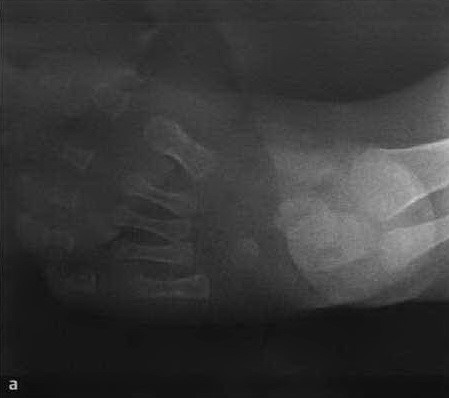

а, b Косолапость в возрасте 5 мес.: а) Рентгенограмма стопы в дорсальной проекции демонстрирует укорочение ахиллова сухожилия, отсутствие наклона пяточной кости от задненижнего до верхнепереднего положения и горизонтальное поражение таранной кости, вызывающее уменьшение таранно-пяточного угла;

b) Рентгенологическое исследование стопы в боковой проекции. Состояние приведения стопы (ось таранной кости латеральнее первой плюсневой кости) и уменьшение таранно-пяточного угла